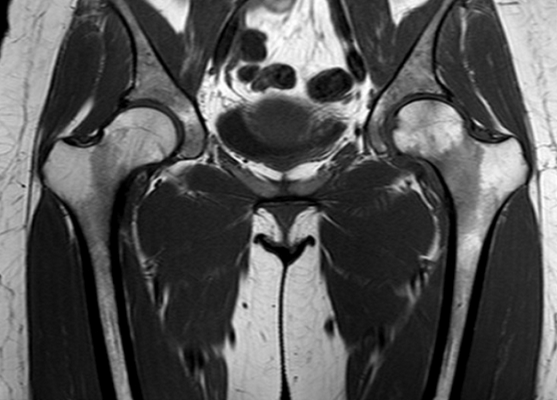

МР-скан коксофеморальных сочленений, вариант нормы

Интерпретацией изображений занимается врач-рентгенолог. В норме на серии томограмм травматических изменений не определяется:

структура костной ткани однородна, без дистрофических признаков;

субхондрального склероза суставных поверхностей нет;

капсула сочленений не утолщена, в полости присутствует небольшое количество синовиальной жидкости с однородным МР-сигналом;

костные крыши вертлужных впадин сформированы правильно, суставные щели равномерные, конгруэнтность (сопоставимость, согласованность) поверхностей сохранена;

целостность связочного аппарата не нарушена;

сигнал хрящевого компонента без особенностей, областей истончения нет;

краевые заострения суставных поверхностей вертлужных впадин отсутствуют;

окружающие мягкие ткани без видимой патологии;

бедренные и тазовые кости в зоне сканирования без очаговых изменений.